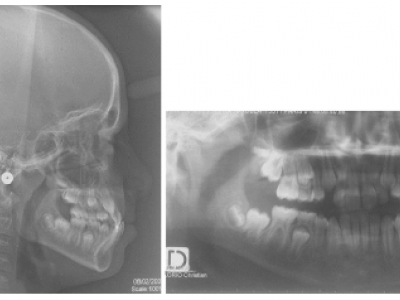

- Le cas numéro 3 est celui d’un garçon de 11 ans, présentant une hypoplasie du prémaxillaire, induisant une prognathie mandibulaire (Fig.17).

L’occlusion est inversée sur les 4 incisives ; les canines maxillaires, n’ayant pas de place, vont faire leur éruption en ectopie vestibulaire. Ici encore, le manque de développement du maxillaire entraîne un manque de place pour les dents définitives. Les secondes prémolaires ne sont pas encore sur l’arcade (Fig. 18).

- Le troisième patient est appareillé avec une plaque à surélévations molaires et vérins d’expansion antérieur et transversal (Fig. 17). Un arc lingual permet de conserver le E-space en maintenant 36 46, et laissera le recul spontané des dents antéro-inférieures.

Des photos (Fig. 18) sont réalisées à la même séance, quand le recouvrement incisif est obtenu, avec et sans appareil. Les plans molaires sont diminués pour obtenir une hauteur correspondant au minimum à la béance molaire afin de ne pas avoir de propulsion à la fermeture. Le rapprochement des incisives libère alors de la place pour les canines (Fig. 19). L’appareil est progressivement retiré ainsi que l’arc lingual, et l’alignement est terminé avec des attaches collées sur toutes les dents (Fig. 20).

Le 3ème cas entrepris plus tardivement, montre que l’appareil fonctionnel a permis une reprise de la croissance de la zone antérieure du maxillaire. Les attaches sont placées dès que le recouvrement positif est obtenu et que la hauteur des plans est diminuée (Fig. 18).

Le patient est revu à 22 ans 8 mois (Fig. 21-23), à la demande du praticien, avec un bilan radiologique (Fig. 24).

Les dents de sagesse ont été extraites, les résultats sont globalement maintenus à l’exception de l’articulé 23/33, aucun fil de contention n’a été collé à l’époque pour prévenir les problèmes parodontaux sur les incisives en cas de récidive éventuelle (Fig.25-26).

On note cependant que le maxillaire et l’étage moyen de la face manquent de relief et de volume, par rapport aux cas entrepris plus tôt, chez lesquels, à l’âge adulte, aucune séquelle de la malocclusion initiale n’est décelable sur le visage. L’utilisation d’un arc lingual pour bloquer les 6 dans le traitement de la classe III est peut-être responsable de la mésialisation secondaire de ces dents et du manque de place apparu par la suite pour les canines inférieures.